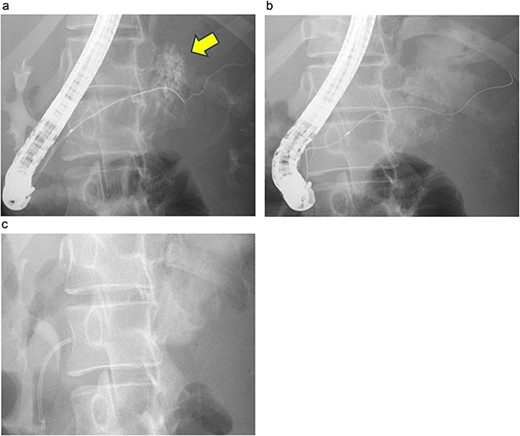

On the fifth day, the ascitic fluid increased in volume, and an open distal pancreatectomy was considered. However, her condition was stable. CT-guided abdominal drainage was performed, and a 10 Fr drainage tube was inserted for peritoneal lavage (Fig. 4). EUS-guided transgastric drainage of the pseudocyst in the omental bursa was performed. The pseudocyst was punctured; a balloon was dilated through the posterior wall of the stomach (Fig. 5a–c), and three tube stents of 7 Fr were implanted (Fig. 5d). The Amy and P-Amy levels in ascites were 9429 and 8877 IU/L, respectively; then, peritoneal lavage was performed daily. On the 12th day, contrast-enhanced CT revealed reduced pseudocyst size (Fig. 6). The patient was discharged on the 16th day (Fig. 7). Three years later, the patient is living her daily life without any complications.

CT of the pelvic region on the fourth day. An increase in ascitic fluid was observed. CT-guided abdominal drainage was performed, and a 10 Fr drainage tube was placed.